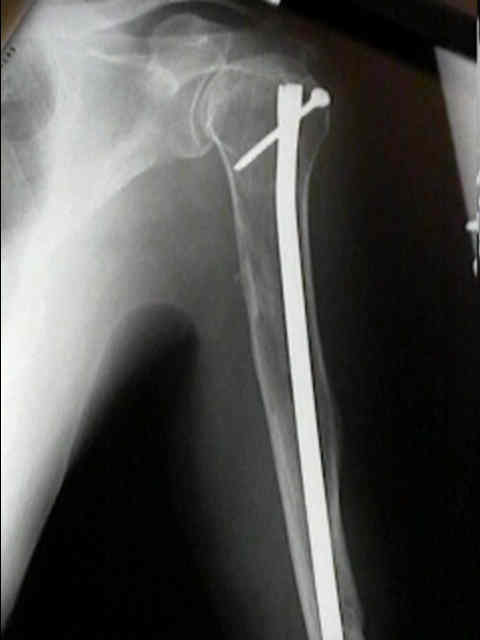

Surgical Fixation

- Treatment of pathologic fracture of the humerus.

Treatment

- myeloma is sensitive to XRT, & reossification of tumor defects may ocurr within several months.